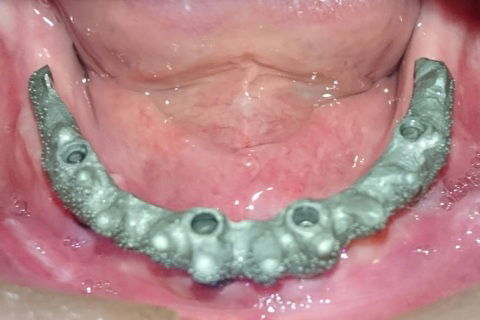

Barras metálicas

Guia multifuncionais!

Prova das barras